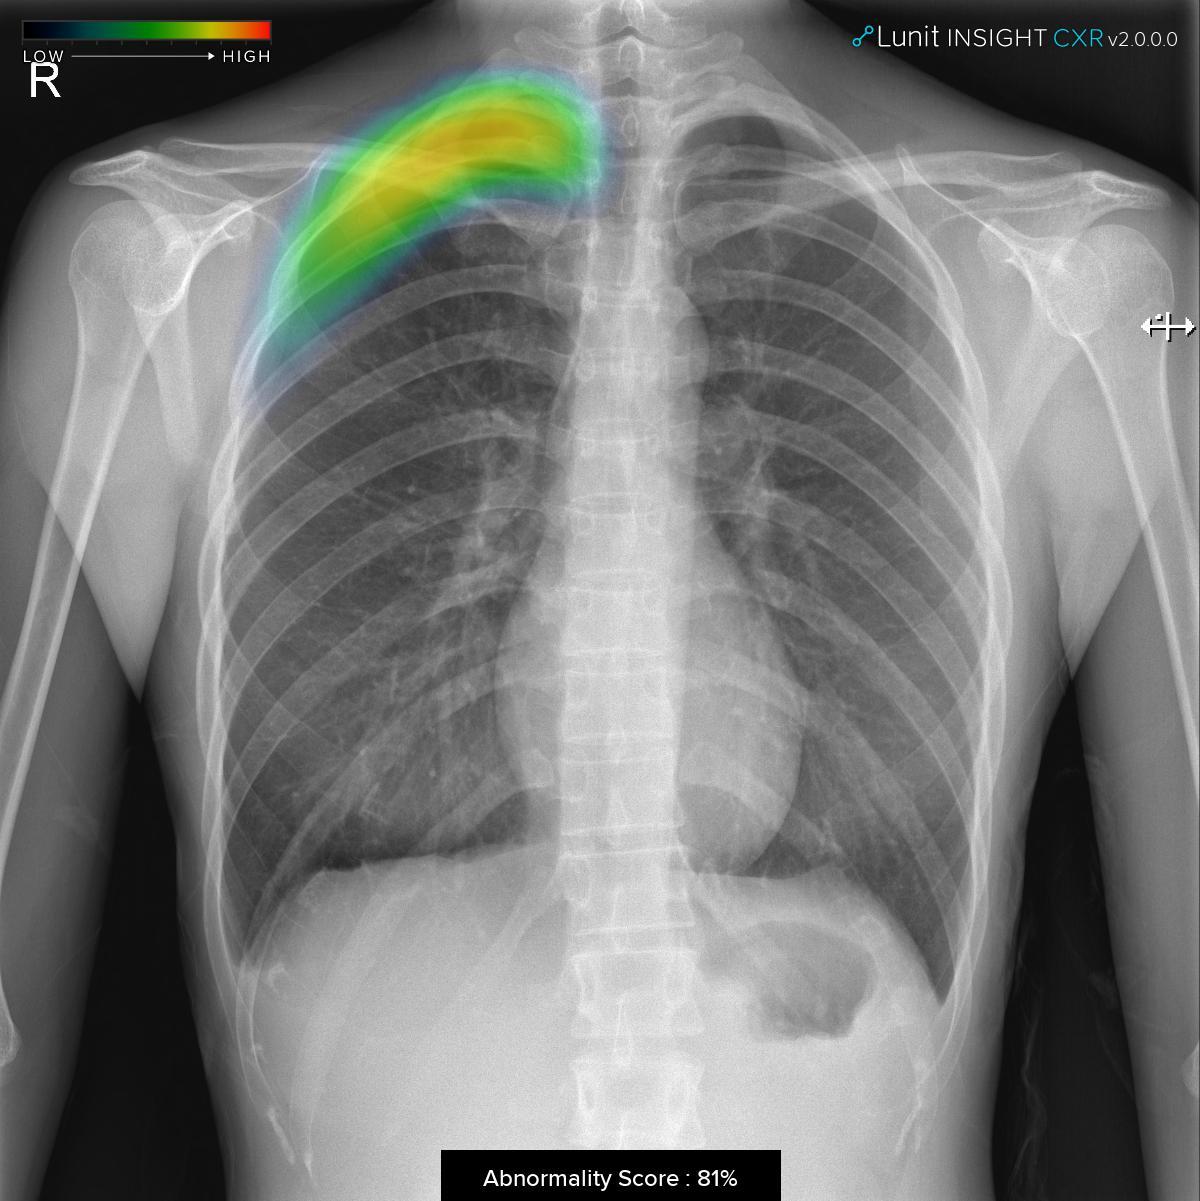

루닛 인사이트 CXR 2는 지난해 허가받은 폐 결절 검출 제품(Lunit INSIGHT CXR)의 업그레이드 버전이다. 루닛의 독자적인 인공지능 기술을 바탕으로 환자의 흉부 엑스레이 사진을 분석해 폐 결절, 폐 경화, 기흉 등의 3가지 주요 폐 비정상 소견을 97~99%의 정확도로 찾아낸다. 의사들의 판독을 보조할 목적으로 설계됐으며 각 질환 의심 부위와 의심 정도를 색상 등으로 표기해 빠르고 정확한 진단을 돕는다.

서범석 루닛 대표는 “앞서 인허가를 받은 폐 결절 검출 제품을 더욱 발전 시켜 흉부 엑스레이 사진 한 장으로 여러 비정상 소견을 한눈에 잡아낼 수 있도록 지속적으로 업그레이드하고 있다”며 “진료 환경에서 루닛 인사이트 CXR 2를 활용할 경우 높은 정확도로 주요 폐 비정상 소견을 발견할 수 있으며, 폐암, 폐렴, 결핵, 기흉 등의 주요 폐 질환을 더 빠르고 정확하게 진단하는 데 큰 도움이 될 것으로 기대한다”고 설명했다.